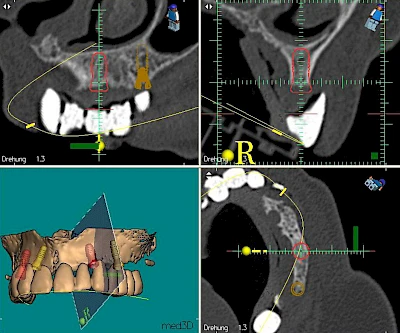

Implantatplanung

Damit Implantate an der richtigen Stelle im Kieferknochen platziert werden könen, gibt es heute vielfältige Möglichkeiten der Planung. In vielen Situationen kann die Erfahrung des Zahnarztes ausreichend sein.

Nicht selten ist jedoch auch eine technisch aufwändigere Vermessung im Vorfeld sinnvoll, z. B.:

- Wenn sich der Kieferknochen abgebaut hat

- Wenn der Nervverlauf im Unterkiefer beachtet werden muss

- Wenn die Ausdehung der Kieferhöhle im Oberkiefer beachtet werden muss

- Wenn wenige Restzähne keine gute Orientierung erlauben

In diesen Fällen kann die Planung mittels verschieden aufwendiger Röntgen-Techniken (Übersichtsaufnahme, DVT) ggf. unter Zuhilfenahme speziell angefertigter Planungsschablonen sinnvoll sein.